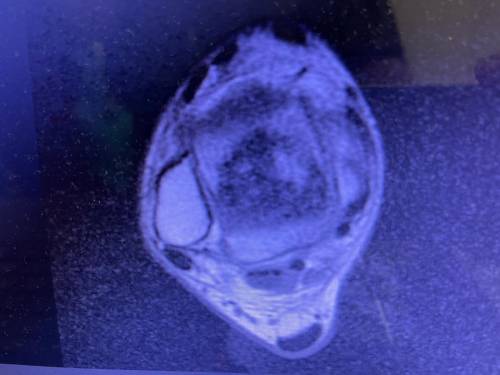

Hastanede yapılan, “Balıkesir’de ilk” nitelikli işlemlerin bir yenisi de Ortopedi ve Travmatoloji Anabilim Dalı Öğretim Üyesi Doç. Dr. Aziz Atik tarafından gerçekleştirildi. Gerçekleştirilen ameliyatla ilgili bilgiler veren Ortopedi ve Travmatoloji Anabilim Dalı Öğretim Üyesi Doç. Dr. Aziz Atik; “Lenf kanseri olan 21 yaşındaki hastamız lenf kanseri tedavisi görerek sağlığına kavuşmuş ancak ilerleyen zamanlarda aldığı tedavilerin yan etkisi olarak ayak bileği kemiğinde çürüme meydana gelmiş. Bize başvuran hastamızın eklem yüzeyi bozulmuş ve hastamız yürümekte zorlanıyor, topallıyordu. Büyük bir lezyonu olan hastamıza büyük lezyonlarda uygulanan en iyi tedavi yöntemi olan ve nadir olarak yapılan bir ameliyatla kadavra donörden kemik ve kıkırdak doku nakli gerçekleştirdik.” ifadelini kullandı. Ülkemizde kemik ve kıkırdak bankası olmadığının altını çizen Doç. Dr. Aziz Atik, yurt dışından bir donör bulmak için çalışmalar yaptıklarını ve yurtdışından kemik bulunduğunda ivedi bir şekilde ameliyatı gerçekleştirdiklerini söyledi. Ameliyatın son derece başarılı geçtiğini belirten Doç. Dr. Aziz Atik, güzel bir eklem düzeyi elde ettiklerini ve ameliyatla genç bir insanın topallamadan, ağrısız yürümesini hedeflendiklerini dile getirdi.